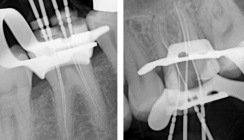

Obwohl die apikale Läsion des Zahnes 44 aufgrund der Größe bereits mehrere Monate bestehen musste, war die Ursache des Zahnarztbesuches die akuten ausstrahlenden Beschwerden des Zahnes 45, welcher bereits vor vielen Jahren mit einer Goldkrone versorgt worden war. Die Ausgangsaufnahme (Abb. 1) zeigte weiterhin eine stark gekrümmte Wurzel mit einem s-förmigen Kanalverlauf am Zahn 44. Diese anatomische Besonderheit erschwert die prognostisch sichere apexnahe Aufbereitung des Wurzelkanalsystems erheblich und stellt den Endodontologen vor besondere Herausforderungen. Beide Zähne wurden nach Leitungsanästhesie trepa­niert, die Pulpakammerböden und die Kanaleingänge dargestellt (Abb. 2). Es zeigte sich bei der intrakoronalen Inspektion eine stark verlängerte Blutung aus dem Wurzelkanalsystem des Zahnes 45, während am Zahn 44 eine deutliche Pusentleerung beobachtet werden konnte.

Nach Spülung mit dreiprozentiger Natriumhypochloridlösung am Zahn 45 wurde eine Arbeitslänge von 21 Millimetern nach elektrometrischer Längenbestimmung gemessen (Abb. 3 und 4). Die Aufbereitung und Reinigung des Wurzelkanalsystems des Zahnes 45 konnte bereits in der ersten Akutbehandlung abgeschlossen werden. Es wurde Ledermix als medikamentöse Einlage auf Arbeitslänge eingebracht und der Zahn provisorisch verschlossen. Die Behandlung des Zahnes 44 beschränkte sich auf die Spülung und sehr feine Son­dierung des Kanalsystems mit einer Hedströmfeile der Größe ISO 08/.02, um die Pusentleerung zu unterstützen. Es wurde ein Kalziumhydroxidpräparat als medikamentöse Einlage eingebracht.